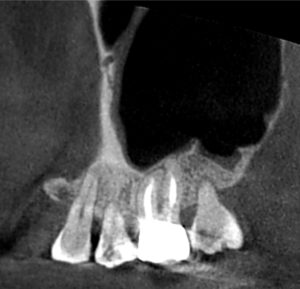

矯正の先生からは、内部吸収をしているので治してほしいと言われてたのですが、レントゲンを撮って良く見てみるとこれは外部吸収でした。

内部吸収というのは、歯の内部が溶けてしまう病気で虫歯とは違います。

虫歯は虫歯菌によって歯が溶かされていくわけですが、内部吸収は歯の中に何らかの理由で破歯細胞という細胞が発生してそいつが歯の中を溶かしてしまう病気です。

外部吸収も同様に虫歯ではなく、破歯細胞が歯の外側から歯を溶かしていき歯の内部に吸収が侵攻する病気です。

上のレントゲンを見ていただくとわかると思いますが、赤矢印の先(歯の外側から)吸収が開始され、歯の内部に吸収が向かい黄色矢印のところまで歯の内部が溶けてしまっているのです。

この病名は、ICR(Invasive Cervical Resorption)「侵襲性歯頸部外部吸収」(しんしゅうせいしけいぶがいぶきゅうしゅう)といいまして、